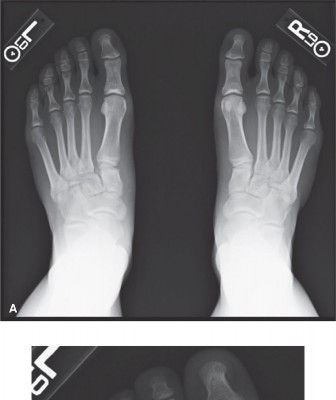

You are asked to evaluate a 40-year-old man with medial forefoot pain. The patient’s primary care provider (P…